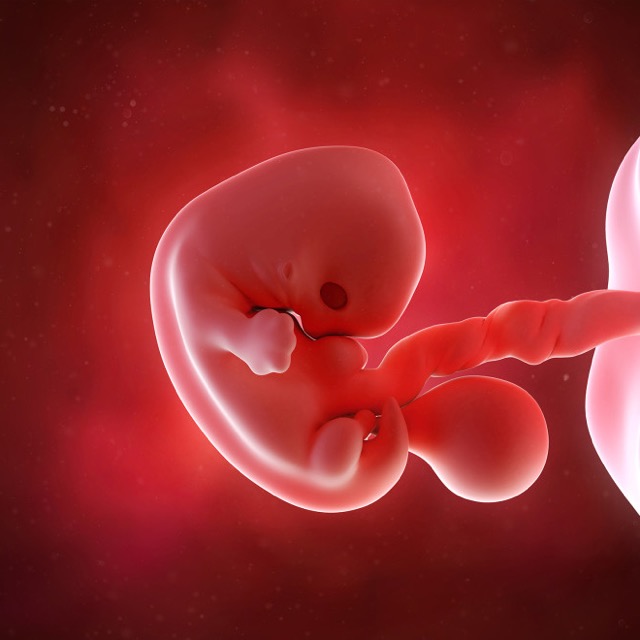

Kenali Perkembangan Janin Usia 7 Minggu Artikel

Kenali Perkembangan Janin Usia 7 Minggu Artikel

Tahapan Perkembangan Janin Minggu Ke 7

Tahapan Perkembangan Janin Minggu Ke 7

Proses Perkembangan Janin Pada Kehamilan Minggu Ke 7

Proses Perkembangan Janin Pada Kehamilan Minggu Ke 7

Hamil 7 Minggu Ditandai Lengan Dan Kaki Siap Tumbuh Apoteker Anda

Hamil 7 Minggu Ditandai Lengan Dan Kaki Siap Tumbuh Apoteker Anda

Perkembangan Janin 7 Minggu Panduan Untuk Ibu Hamil

Perkembangan Janin 7 Minggu Panduan Untuk Ibu Hamil

Perkembangan Janin 7 Minggu Bumil Wajib Tahu

Perkembangan Janin 7 Minggu Bumil Wajib Tahu

Perkembangan Janin 7 Minggu Kehamilan Hello Sehat

Perkembangan Janin 7 Minggu Kehamilan Hello Sehat

Perkembangan Janin Usia 7 Minggu Bidanku Com

Perkembangan Janin Usia 7 Minggu Bidanku Com

Hamil 7 Minggu Seperti Apa Perkembangan Janin

Hamil 7 Minggu Seperti Apa Perkembangan Janin